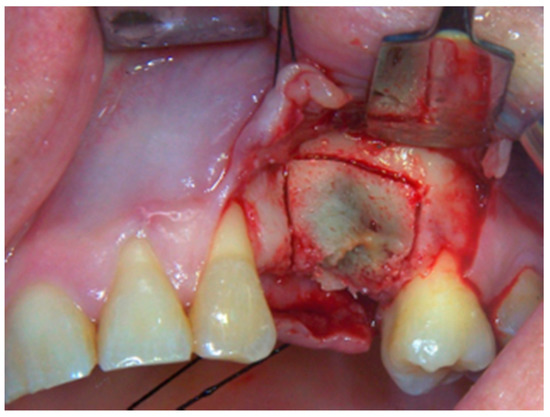

2. Materials and Methods

3. Results

4. Discussion